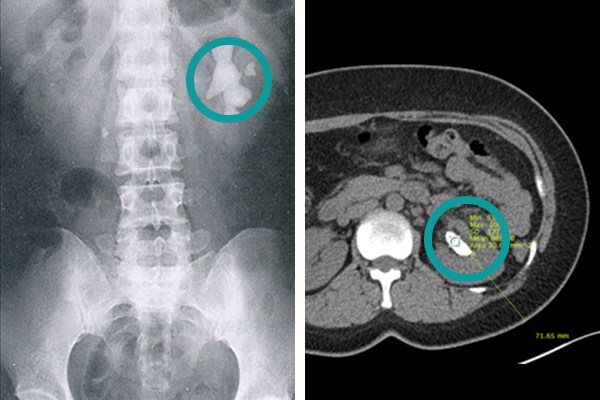

[ ¿ä·Î°á¼® ȯÀÚÀÇ ½ÅÀå¿ä°ü¹æ±¤´Ü¼øÃÔ¿µ(KUB) (ÁÂ) º¹ºÎCT ¿µ»ó (¿ì) ]